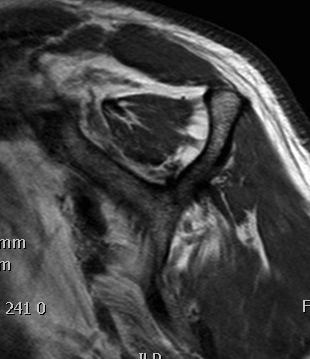

MRI

Look for

- supraspinatus / infraspinatus / subscapularis / long head of biceps pathology

- partial verus full thickness

- size of tear in coronal and sagittal planes

- retraction

- atrophy / fatty infiltration

Full thickness rotator cuff tears

Partial bursal sided tear Partial articular sided tears

Subscapularis tears

Small full thickness rotator cuff tear of supraspinatus - retracted to footprint

Large full thickness tear of supraspinatus and infraspinatus tendon - retracted to midhumeral head

Massive rotator cuff tear of the supraspinatus and infraspinatus tendon - retracted to glenoid